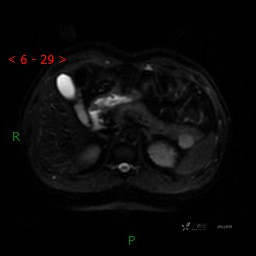

MRI(T1WI+T2WI-fs+DWI+ADC)